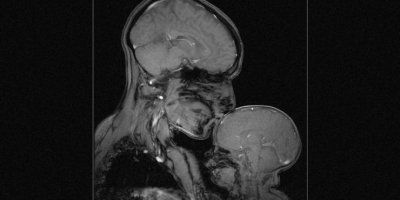

Neuroznanstvenica i majka dvomjesečnog sinčića snimila je nevjerojatnu sliku magnetske rezonancije koja pokazuje snažnu vezu između majke i djeteta.

Snimka koja se pojavila na YouTubeu već je pregledana više od dva miliona puta.